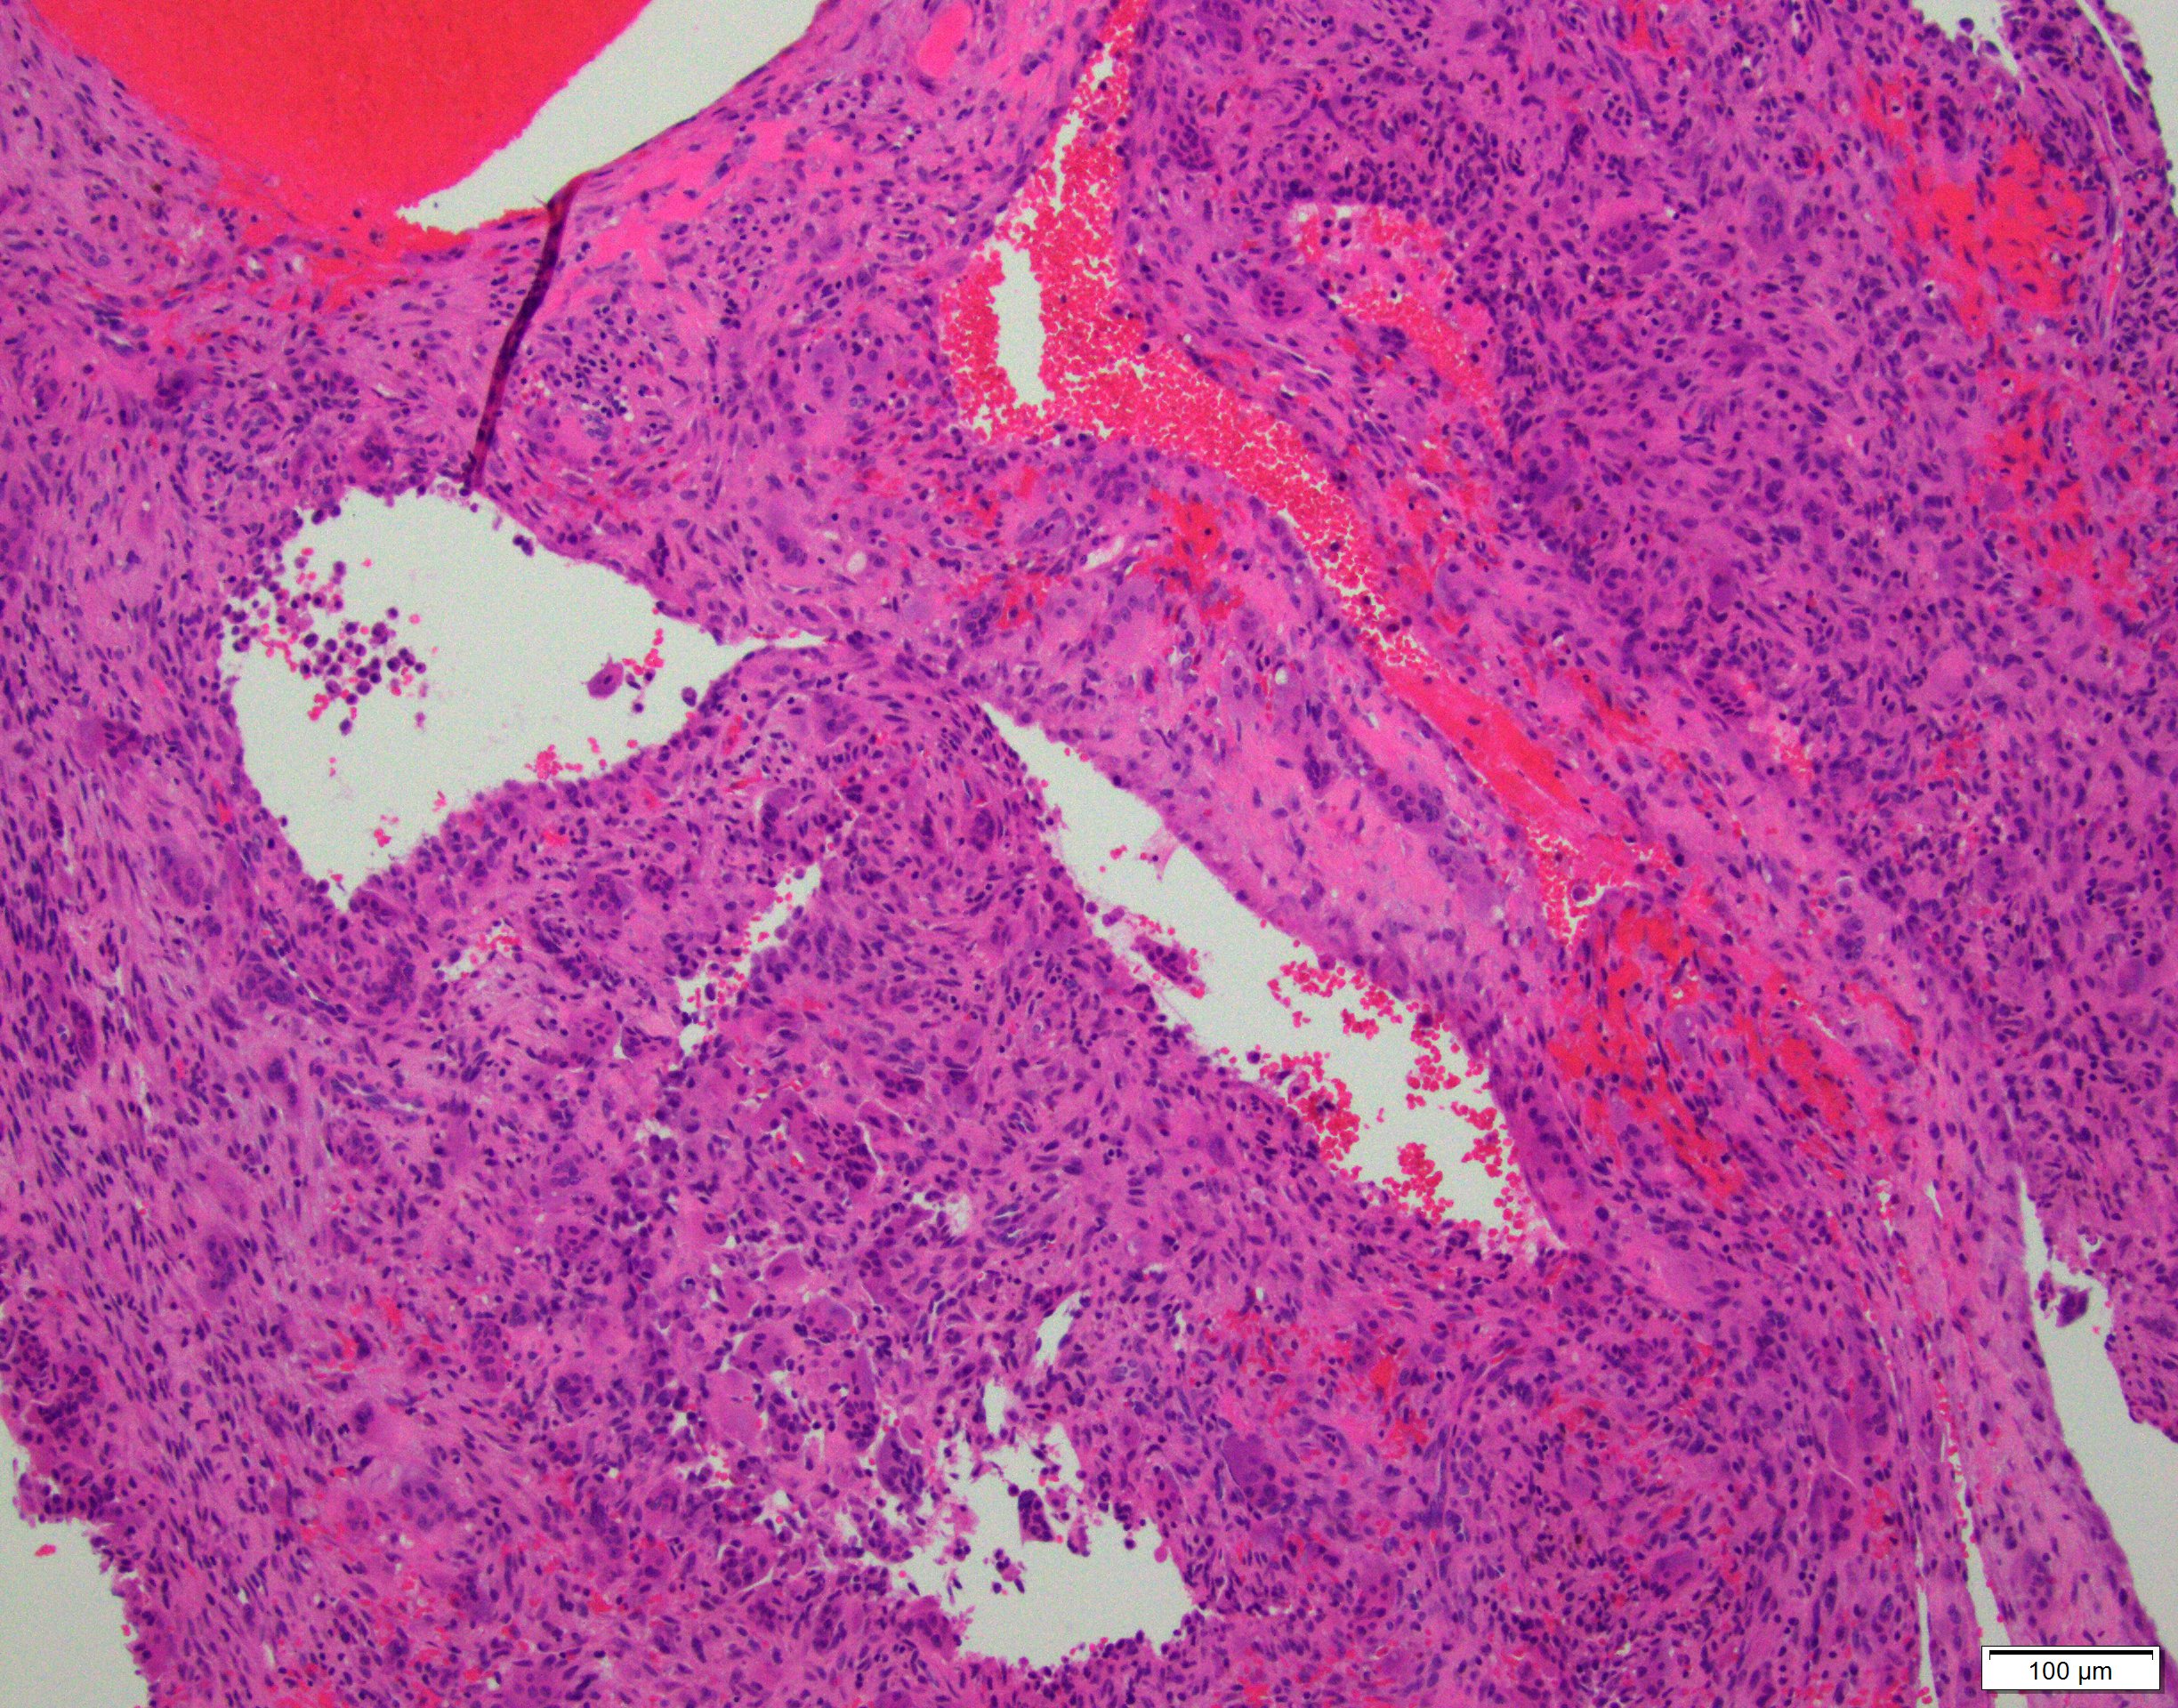

- Multiloculated cystic lesion

- Blood filled cystic spaces separated by cellular septa containing fibroblasts, giant cells and woven bone

- Calcified, basophilic material (blue reticulated chondroid-like material)

- Necrosis not common but mitotic activity is easily identified

- No cytologic atypia (Am J Clin Pathol 2015;143:823)

- Numerous giant cells in connective tissue that line large sinusoidal spaces

Microscopic (histologic) images

Contributed by Elham Nasri, M.D. and Kelly Magliocca, D.D.S., M.P.H.

A. Aneurysmal bone cyst. The H&E shows cystic spaces with stromal giant cells. Rearrangement of USP6 gene confirms the diagnosis in the above clinical and radiographic context.